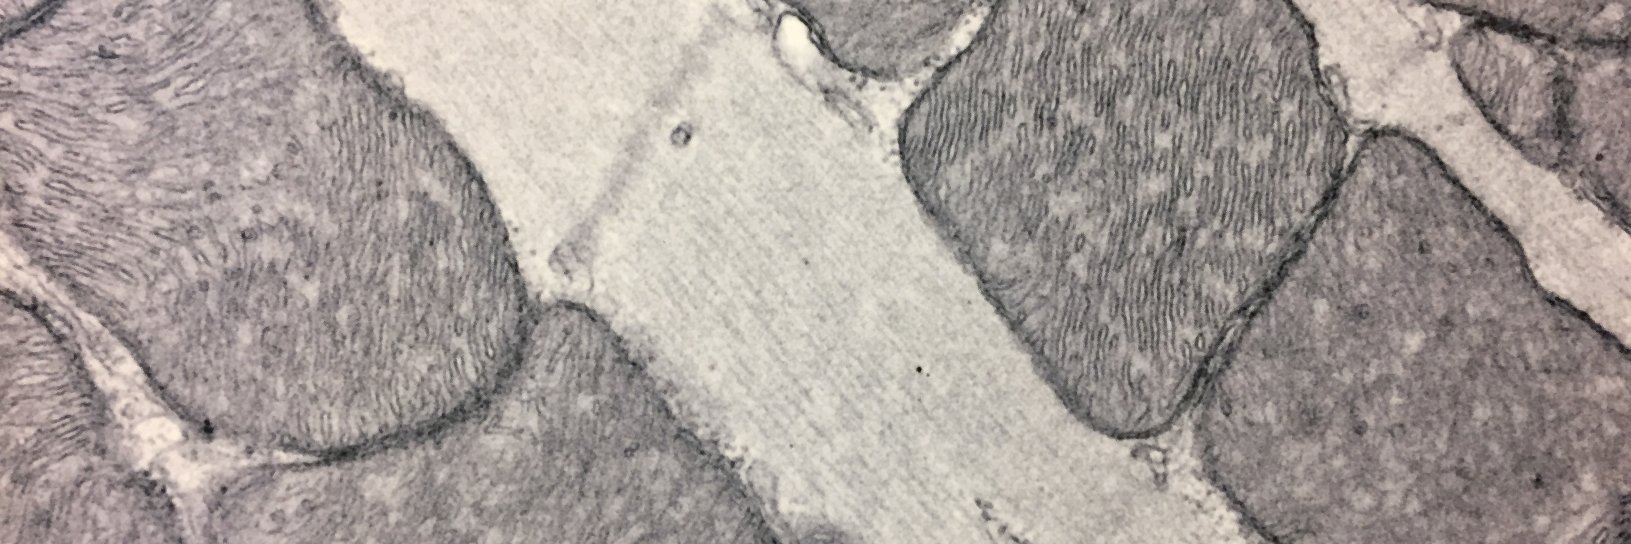

The mitochondrial citrate carrier SLC25A1 mediates key metabolic transitions during cardiac morphogenesis through epigenetic regulation of histone acetylation, ultimately supporting structural maturation of the embryonic heart. @KwongLab nature.com/articles/s4200…